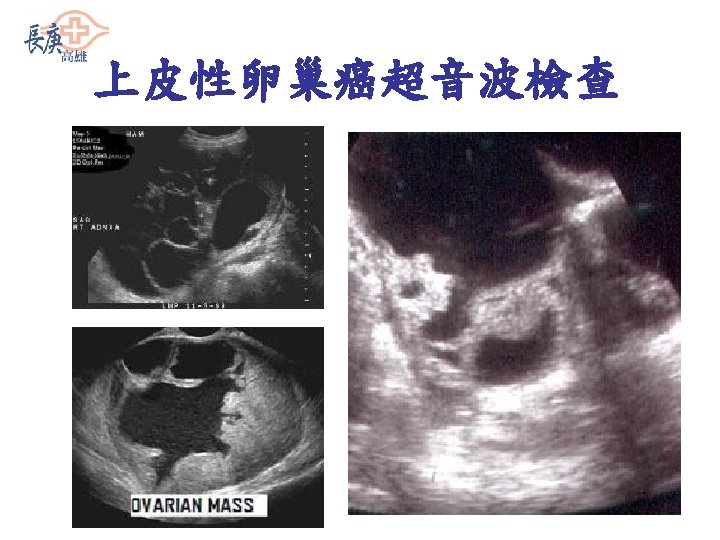

上皮性卵巢癌的預防 Ø 對於有上皮性卵巢癌或乳癌家族史的人,若 經評估檢驗發現確有基因上的風險 (genetically defined risk),則建議進 行目標性篩檢(targeted screening programs),加強卵巢與腹膜之監測: 1. 每半年做含彩色都卜勒的陰道超音波 2. 測血中CA 125 值 3. 骨盆腔內診 NCCN (National Comprehensive Cancer Network) Practice Guidelines in Genetic /Familial High-Risk Assessment, version 1. 2002. Standards, Options and Recommendations. Clinical practice guidelines for cancer care from the French National Federation of Cancer (FNCLCC). Ovarian cancer. Bri J Cancer 2001; 84(Suppl 2): 18 -23.